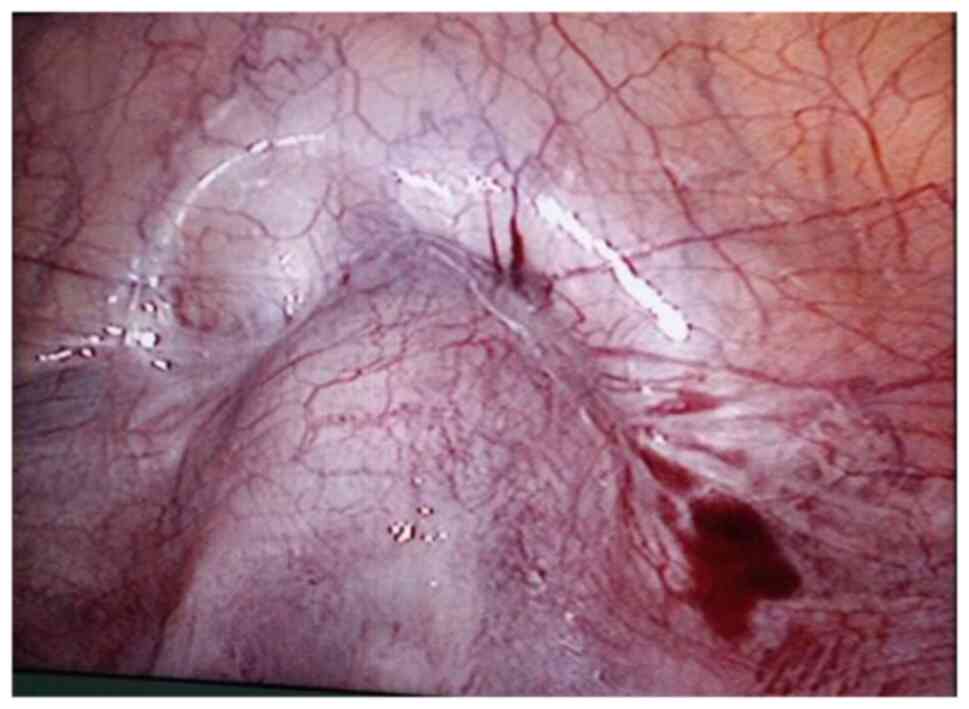

The surgical procedure was as follows: Laparoscopy was performed under general anesthesia in the supine lithotomy position. Laparoscopy displayed a bulging in the lower uterine segment (Fig. 1). Subsequently, a 12 IU vasopressin solution was injected into the uterus. The bladder peritoneum was incised to expose the pregnancy scar; a bulging was noted comprised of blood vessels and gestational tissues. The gestational tissue was rapidly removed with grasping forceps, scissors and an aspirator (Figs. 2 and 3). This procedure was performed as quickly as possible. The myometrial scar was resected and stanched by bipolar coagulation. Finaly, a continuous suture with an absorbable suture (1-0) was used to close the uterine wound (Fig. 4).

Resection of the scar with gestational tissue (patient 5).

Figure 4

The visual appearance of the uterus following sutures (patient 5).